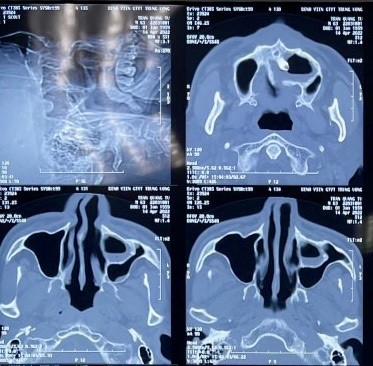

CT Scanner xoang: có hình ảnh khối cản quang (mật độ tương tự mô xương) nghi là một chiếc răng nằm trong xoang hàm.